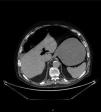

Varón de 82años con distensión y dolor abdominal generalizado, acompañado de vómitos oscuros de aspecto retencionista y deposiciones diarreicas. En radiografía simple de abdomen (fig. 1) existe aire en pared gástrica y dilatación de asas intestinales, por lo que se solicita TC abdominal (fig. 2) donde se observa gas intramural asociado a dilatación gástrica, neumoperitoneo (fig. 3) y gas en vena porta (fig. 4). Se realiza laparotomía exploradora y se observa un estómago distendido con burbujas de gas en su serosa, sin signos de necrosis transmural ni perforación. La gastroscopia intraoperatoria muestra una mucosa necrótica-ulcerada sin sangrado espontáneo en cara posterior, cuerpo y curvatura mayor. Dados estos hallazgos se opta por no realizar ningún acto quirúrgico más. Se aísla Lactobacillus jensenii en hemocultivos y se trata con meropenem+linezolid. El paciente evoluciona favorablemente con mejoría en TC abdominal de control, recibiendo el alta hospitalaria. La gastritis enfisematosa es una patología rara producida por la translocación de microorganismos productores de gas dentro de las paredes gástricas. Hasta en un 42.4%1 de los casos no es posible aislar el causante y conlleva una mortalidad de hasta el 60%2. El TC es la prueba diagnóstica de elección, siendo fundamental el diagnóstico precoz y un tratamiento de soporte vital con antibioterapia de amplio espectro. Se reserva la cirugía cuando existe falta de respuesta al tratamiento conservador, sepsis severa o perforación gástrica3.